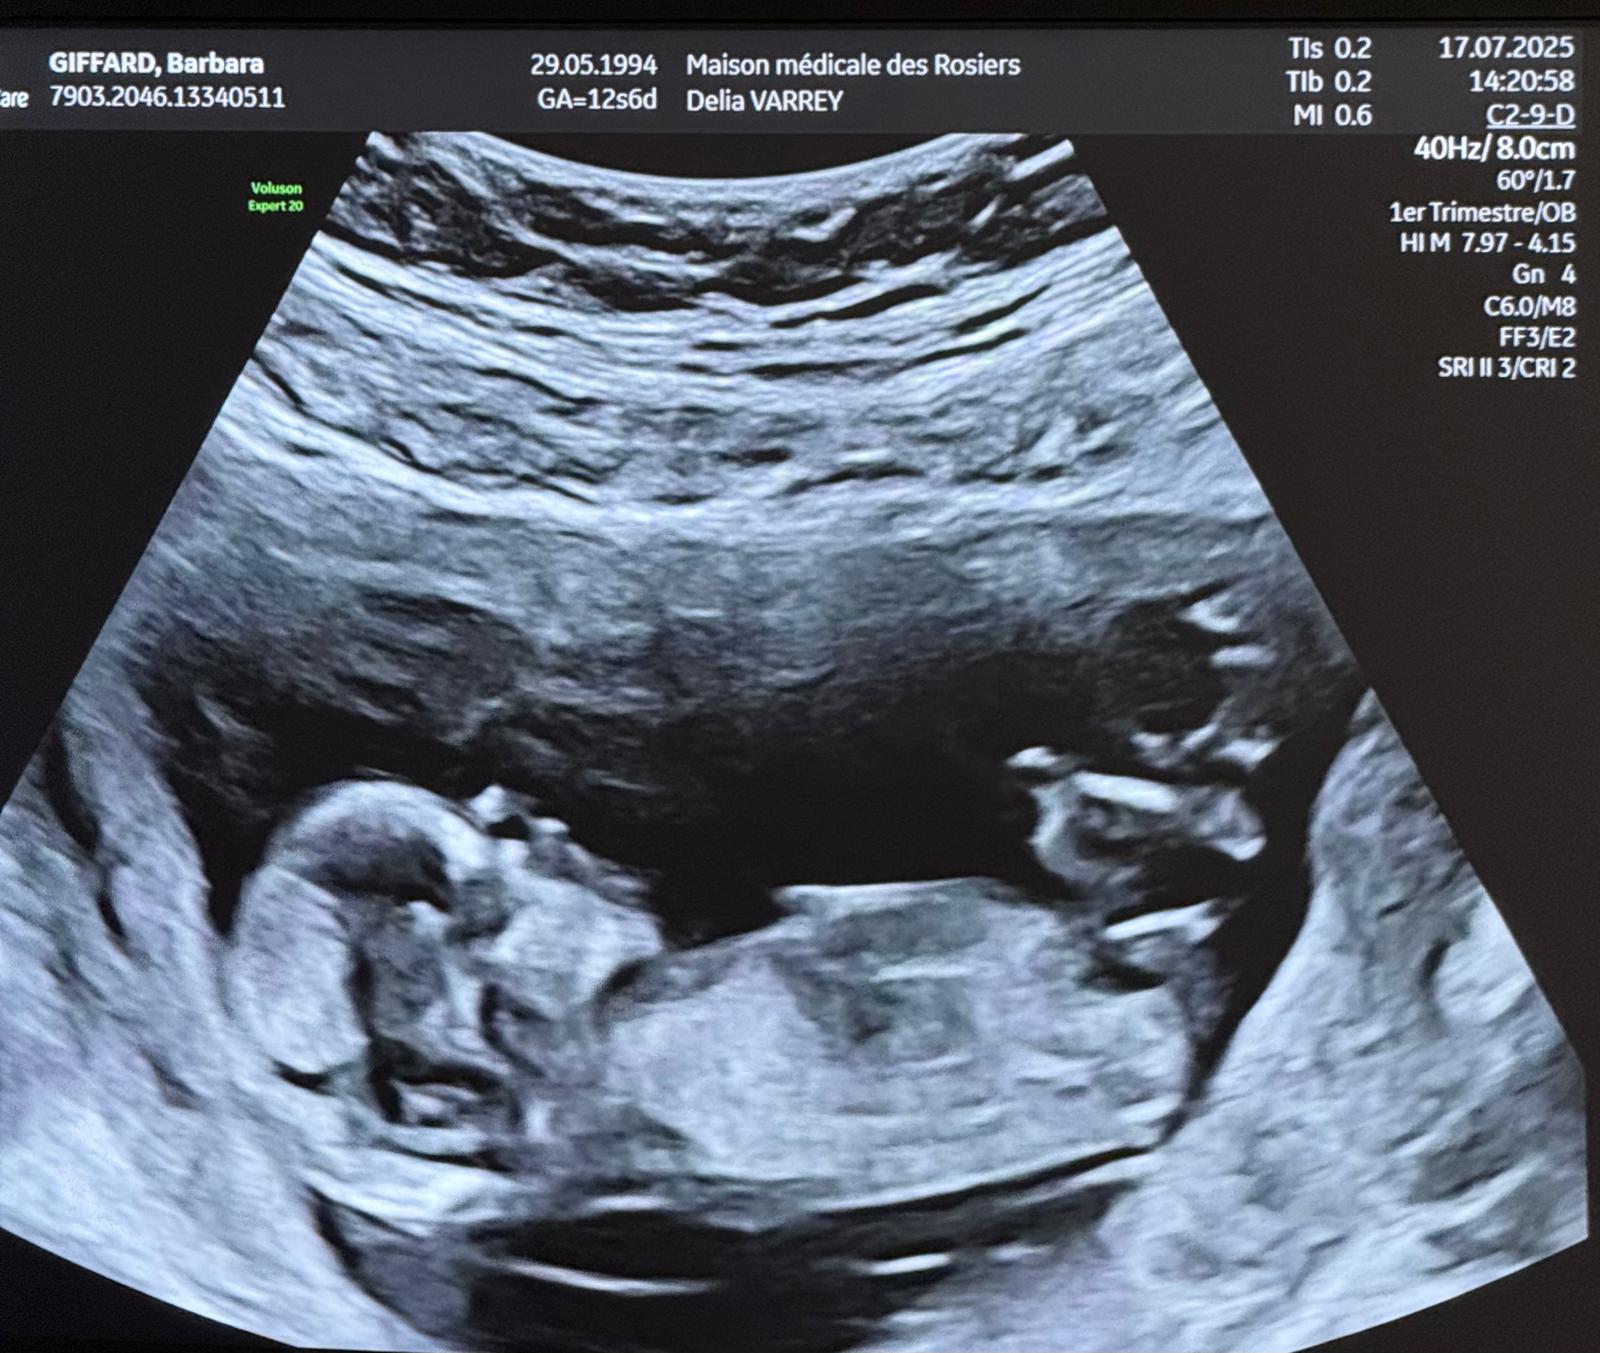

La Surprise

Bon, c’est bien sympa les remerciements, l’amour, les fleurs, les discours, les photos… mais soyons honnêtes : si vous êtes arrivés jusqu’ici, c’est surtout pour la surprise, non ? 😏

Alors oui, on vous voit venir avec vos grands yeux curieux et vos clics frénétiques.

On ne dira rien (enfin… pas tout de suite). Disons juste que cette année n’a pas fini d’être riche en émotions et en belles aventures pour nous… 🎁✨

On a acheté un appartement en janvier, on s’est mariés en juin… quelle pourrait bien être la suite ? 🧐

Vous voulez vraiment savoir ?

Allez, cliquez ci-dessous… mais préparez-vous à dire “Ooooohhh !”

👉 Voir la surprise